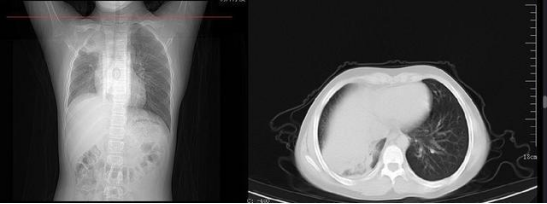

在 2020 年新冠疫情剛開始時,病毒會對肺部造成明顯影響,肺部 CT 變化也是確診的重要標志。而如今奧密克戎時代,大約還是有 10% 的感染者會發展為普通型或重癥,表現出輕重不一的肺炎表現。

武漢一 12 歲男孩感染新冠后,家長擔心去醫院會交叉感染,于是在家硬扛,咳嗽一周不就醫,后來家長發現癥狀沒有好轉,甚至開始嘔吐,這才將他送醫院就診,醫生一查已發展成肺炎,一側肺部已經成了“白肺”。盡管經過治療,男孩的癥狀已經好轉,但也留下了后遺癥——肺部纖維化。

同濟大學附屬上海市肺科醫院呼吸監護室副主任醫師張黎就“白肺”問題進行解讀:“重癥的白肺患者,死亡率在 40% 以上,還是有一部分人是可以治愈的。但是要想讓肺恢復到本來干干凈凈的狀態,是比較難的,絕大部分患者會留下肺部纖維化的后遺癥。之前有專家統計過,在感染新冠德爾塔毒株并康復一年后,患者的肺功能會恢復,但是恢復態勢不會保持太久就會呈下降趨勢,且這種下降是不可逆的。”

《Nature Medicine 》2021 年發表了:Post-acute COVID-19 syndrome,研究指出呼吸困難在 60~100 天的隨訪期內的發生率為 42%~66%,有 6.6% 的患者因持續低氧血癥需要補充氧氣。患者出院后 3 個月評估發現約 25% 的輕度至中度病例存在纖維化,在重癥病例居多的隊列中,約 65% 的康復者存在肺纖維化。

與安慰劑組相比,人臍帶間充質干細胞治療組全肺病變體積改善了 10.8%,并且人臍帶間充質干細胞治療組在每一個隨訪節點都顯示出固體組分病變體積比例減少。此外,人臍帶間充質干細胞組有 17.9% 的患者在 12 個月時 CT 圖像變為正常,而安慰劑組沒有。

每次隨訪時發現,人臍帶間充質干細胞組的相關癥狀發生率均低于安慰劑組,中和抗體均為陽性,中位抑制率分別為 61.6% 和 67.6%。兩組術后 1 年隨訪不良事件及 12 個月腫瘤標志物比較無顯著性差異。目前的研究表明,在 12 個月的隨訪中,CT 圖像所發現的肺部病變只有在人臍帶間充質干細胞治療的患者中才能完全解決。